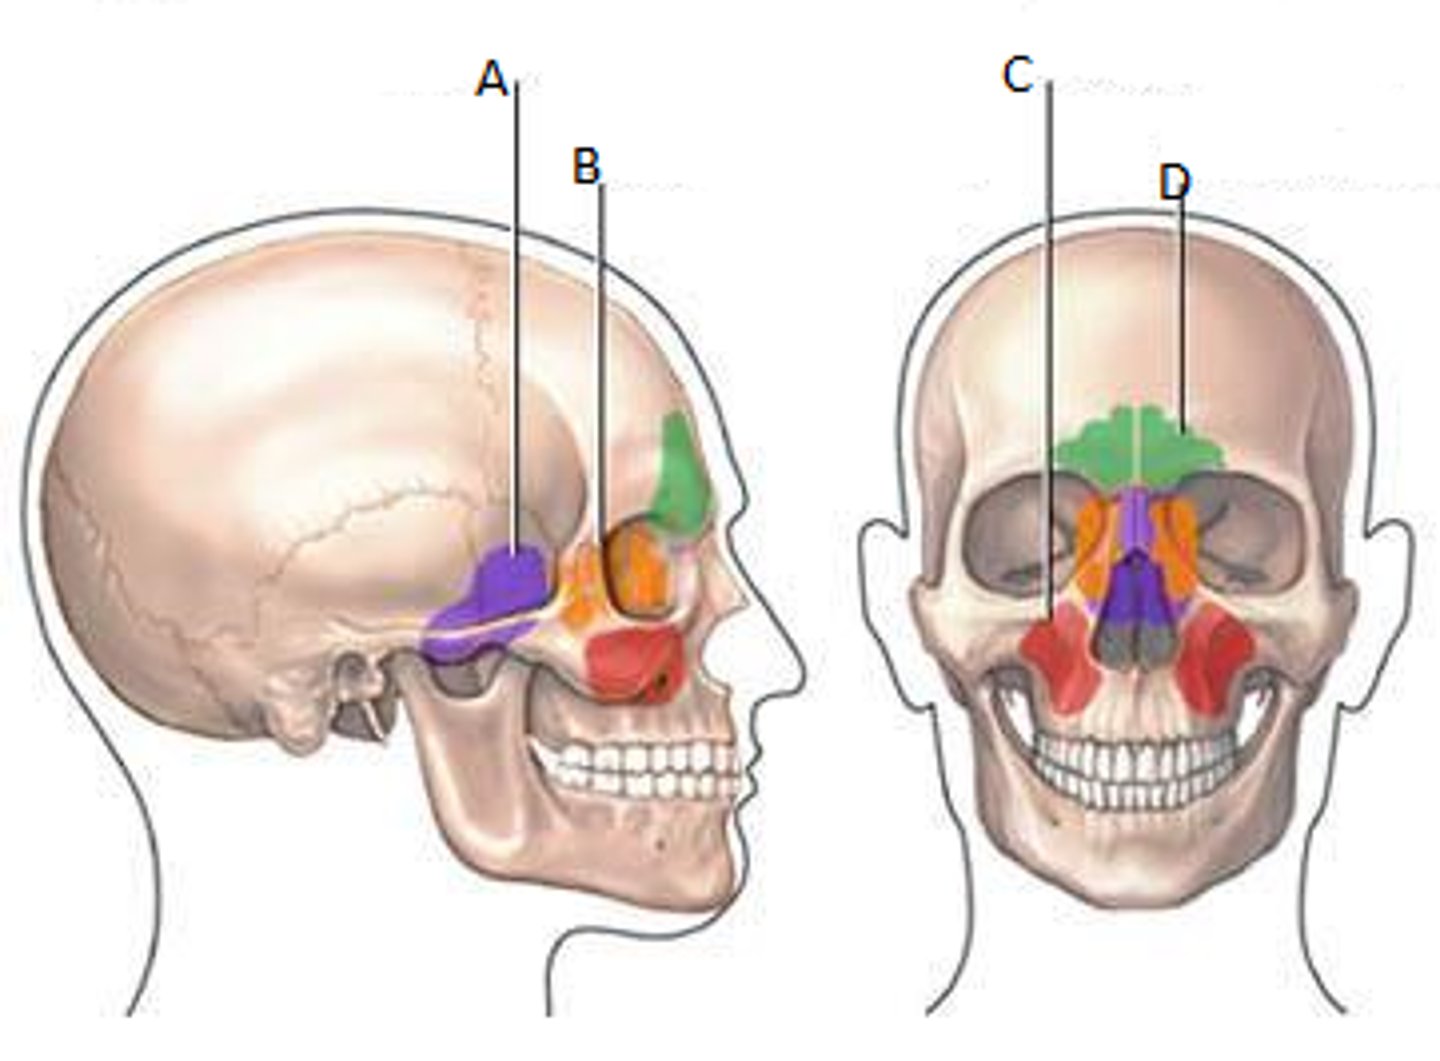

Frontal sinuses

Green

Sphenoid sinuses

Orange

Ethmoid sinuses

Purple

Maxillary sinuses

Red